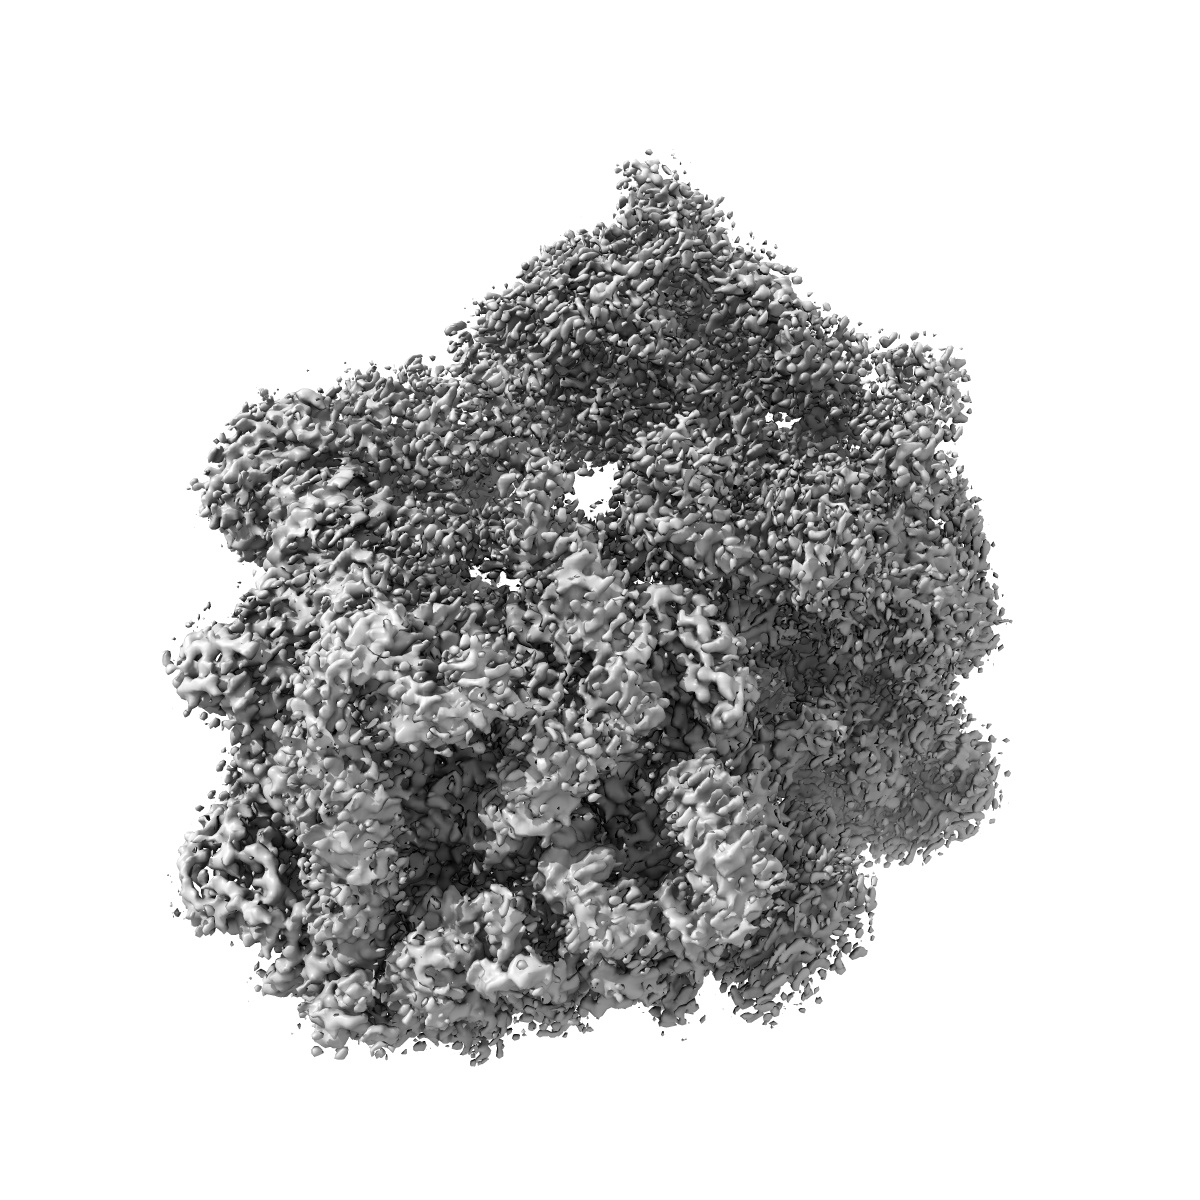

EMD-10079

Single-particle

3.58 Å

Erythromycin Resistant Staphylococcus aureus 70S ribosome (delta R88 A89 uL22).

Sample Organism: Staphylococcus aureus

Sample: Erythromycin Resistant Staphylococcus aureus 70S ribosome (delta R88 A89 uL22) in complex with erythromycin.

Fitted models: 6s13

Deposition Authors: Halfon Y, Matozv D

Exit tunnel modulation as resistance mechanism of S. aureus erythromycin resistant mutant.

Halfon Y, Matzov D, Eyal Z , Bashan A , Zimmerman E, Kjeldgaard J , Ingmer H , Yonath A

(2019) Sci Rep , 9 , 11460 - 11460